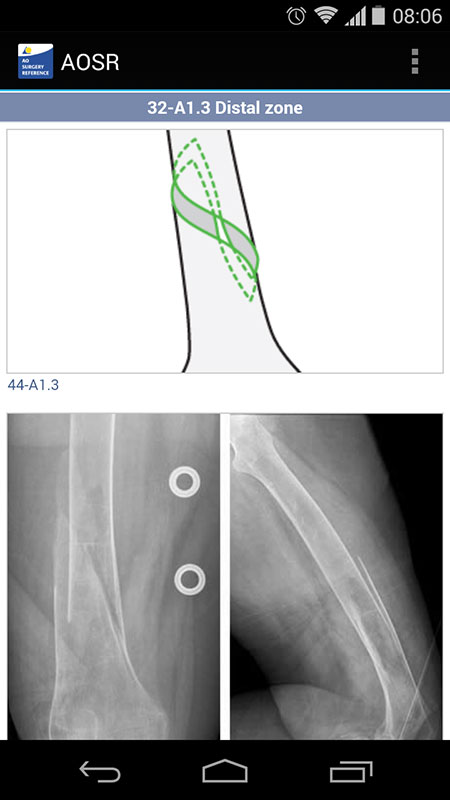

Choosing the area will automatically take us to the Diagnosis tab, showing all the major types of femur shaft fractures, including simple, wedge and complex fractures. Each of these types contains sub-types, i.e. spiral, oblique, bending, fragmented, segmented, etc. You can learn more about them by tapping on the 'i' button, which opens a new page with nice illustrations and X-ray images of the fracture.

Since our patient has simple spiral fracture (or 32-A1 according to the AO/OTA Classification of Fractures and Dislocations), tapping on this diagnosis opened the Decision tab, which provides a lot of helpful information about the most appropriate type of treatment for that type fracture (operative or non-operative), as well as general considerations.